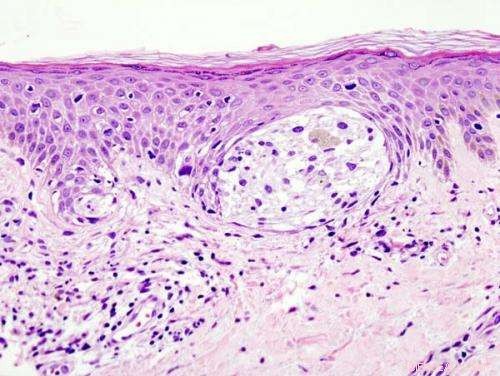

Melanoma in skin biopsy with H&E stain — this case may represent superficial spreading melanoma. Credit: Wikipedia/CC BY-SA 3.0

Melanoma is the deadliest form of skin cancer, with over 232,000 new cases and 55,000 deaths per year worldwide. Those with light-skin or red hair are often prone to hard-to-detect melanomas, often caused by properties of pigments within skin called melanins. People with fair skin have a higher concentration of the melanin known as pheomelanin in their skin, and a corresponding higher probability of developing melanoma—in particular, a difficult-to-detect subtype known as amelanotic melanoma. In high concentrations, pheomelanin is responsible for the orange-reddishness in hair, but is essentially invisible in skin.

While eumelanin, the brown-black pigment found in most melanomas, can be easily seen, the light colored pheomelanin is difficult to detect; even with advances in modern microscopy, understanding the pheomelanin molecule and its role in melanoma has eluded scientists.